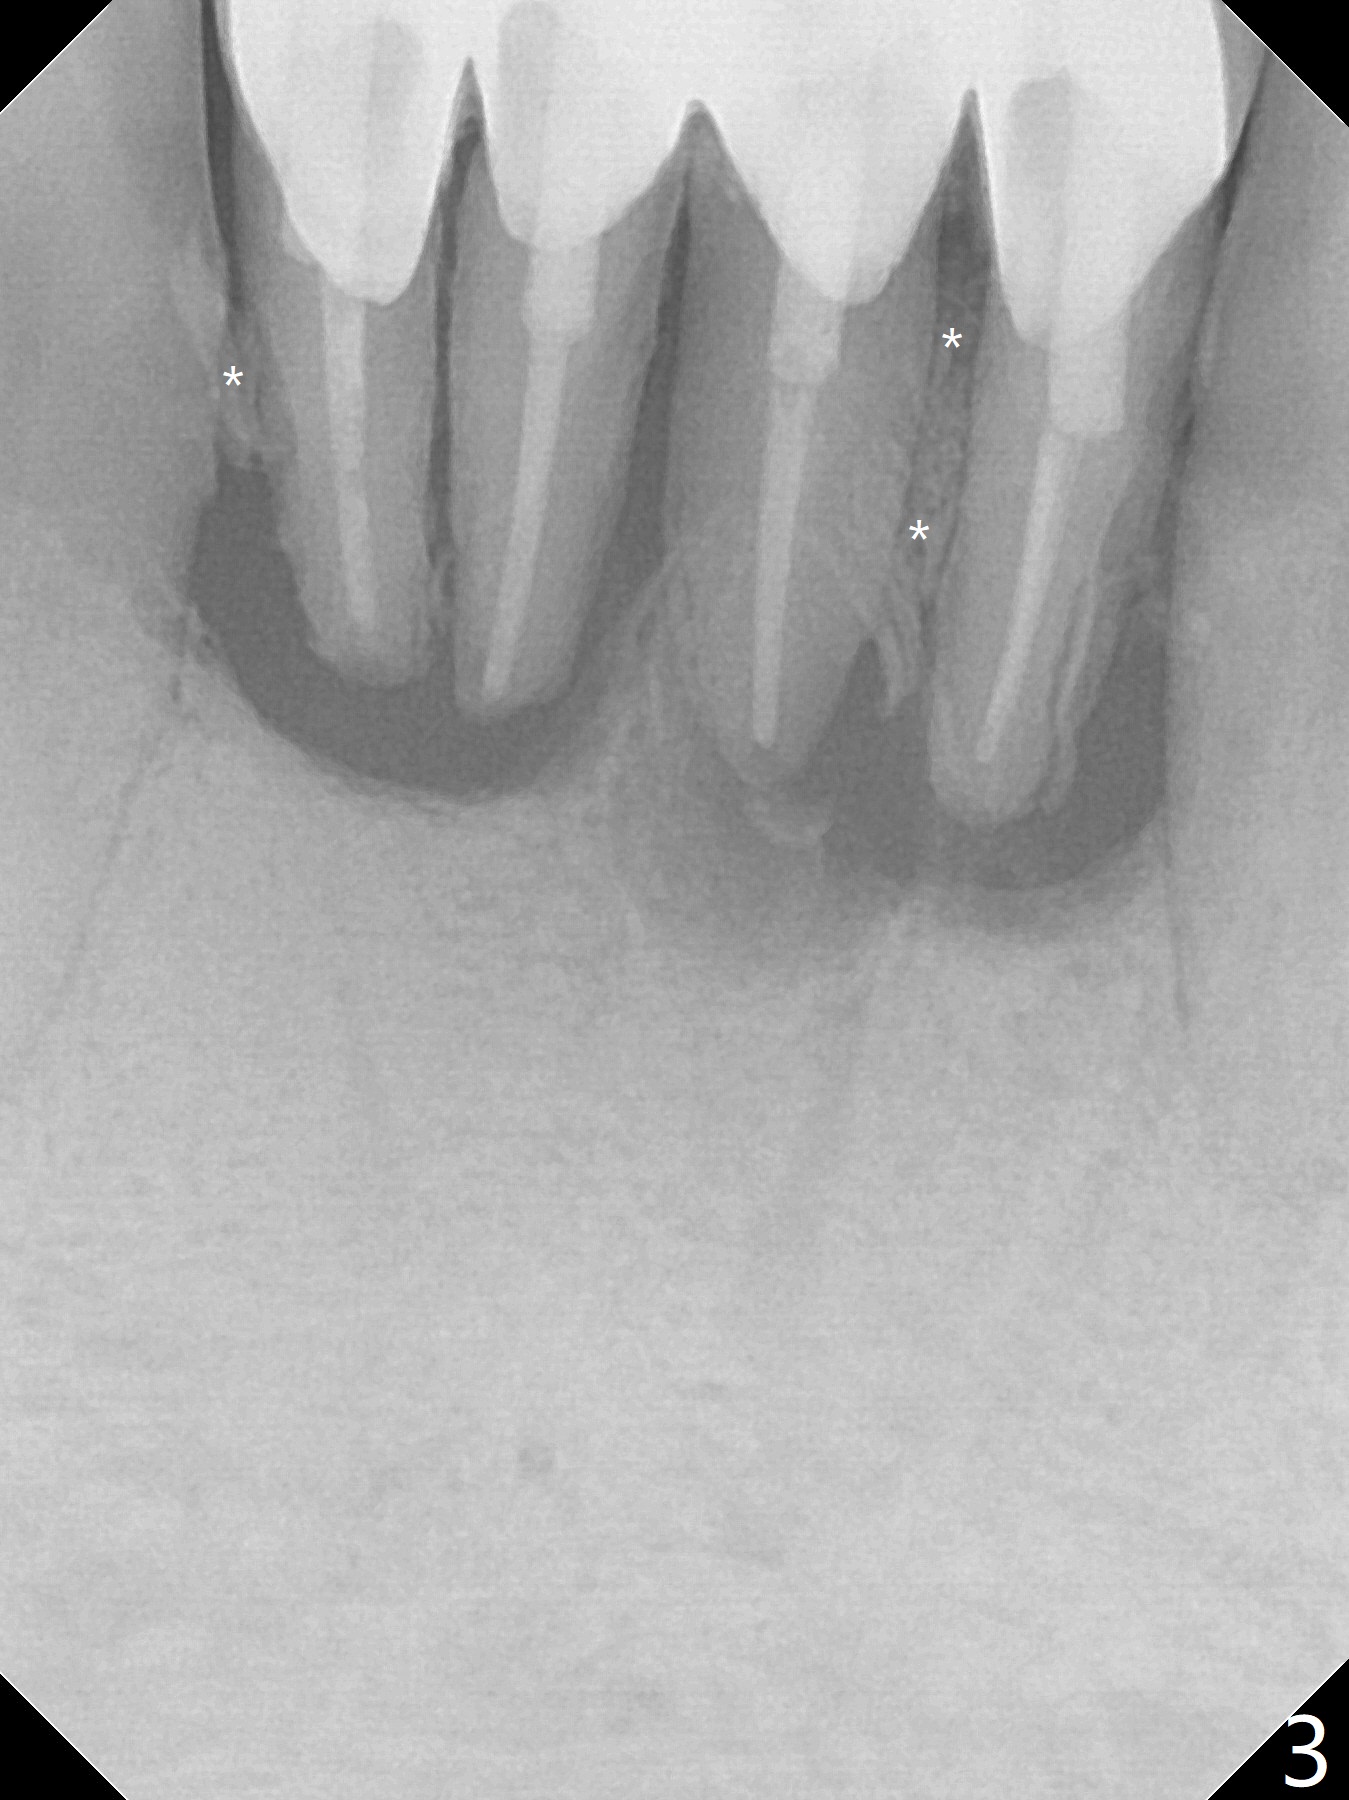

A 58-year-old man with splinted crowns at #23-26 has buccal abscess and lingual gingival recession at #25 and 26 (Fig.1,2). Large periapical radiolucency involves all of the 4 incisors (Fig.3). Note residual crestal bone between the incisors (*). It appears that a 1-piece implant with 4 mm cuff (Fig.4 pink) should be placed on the right side, while a longer 1-piece implant (23 mm) with shorter cuff (1.5 mm) on the left side. A provisional FPD will be fabricated from a stent.